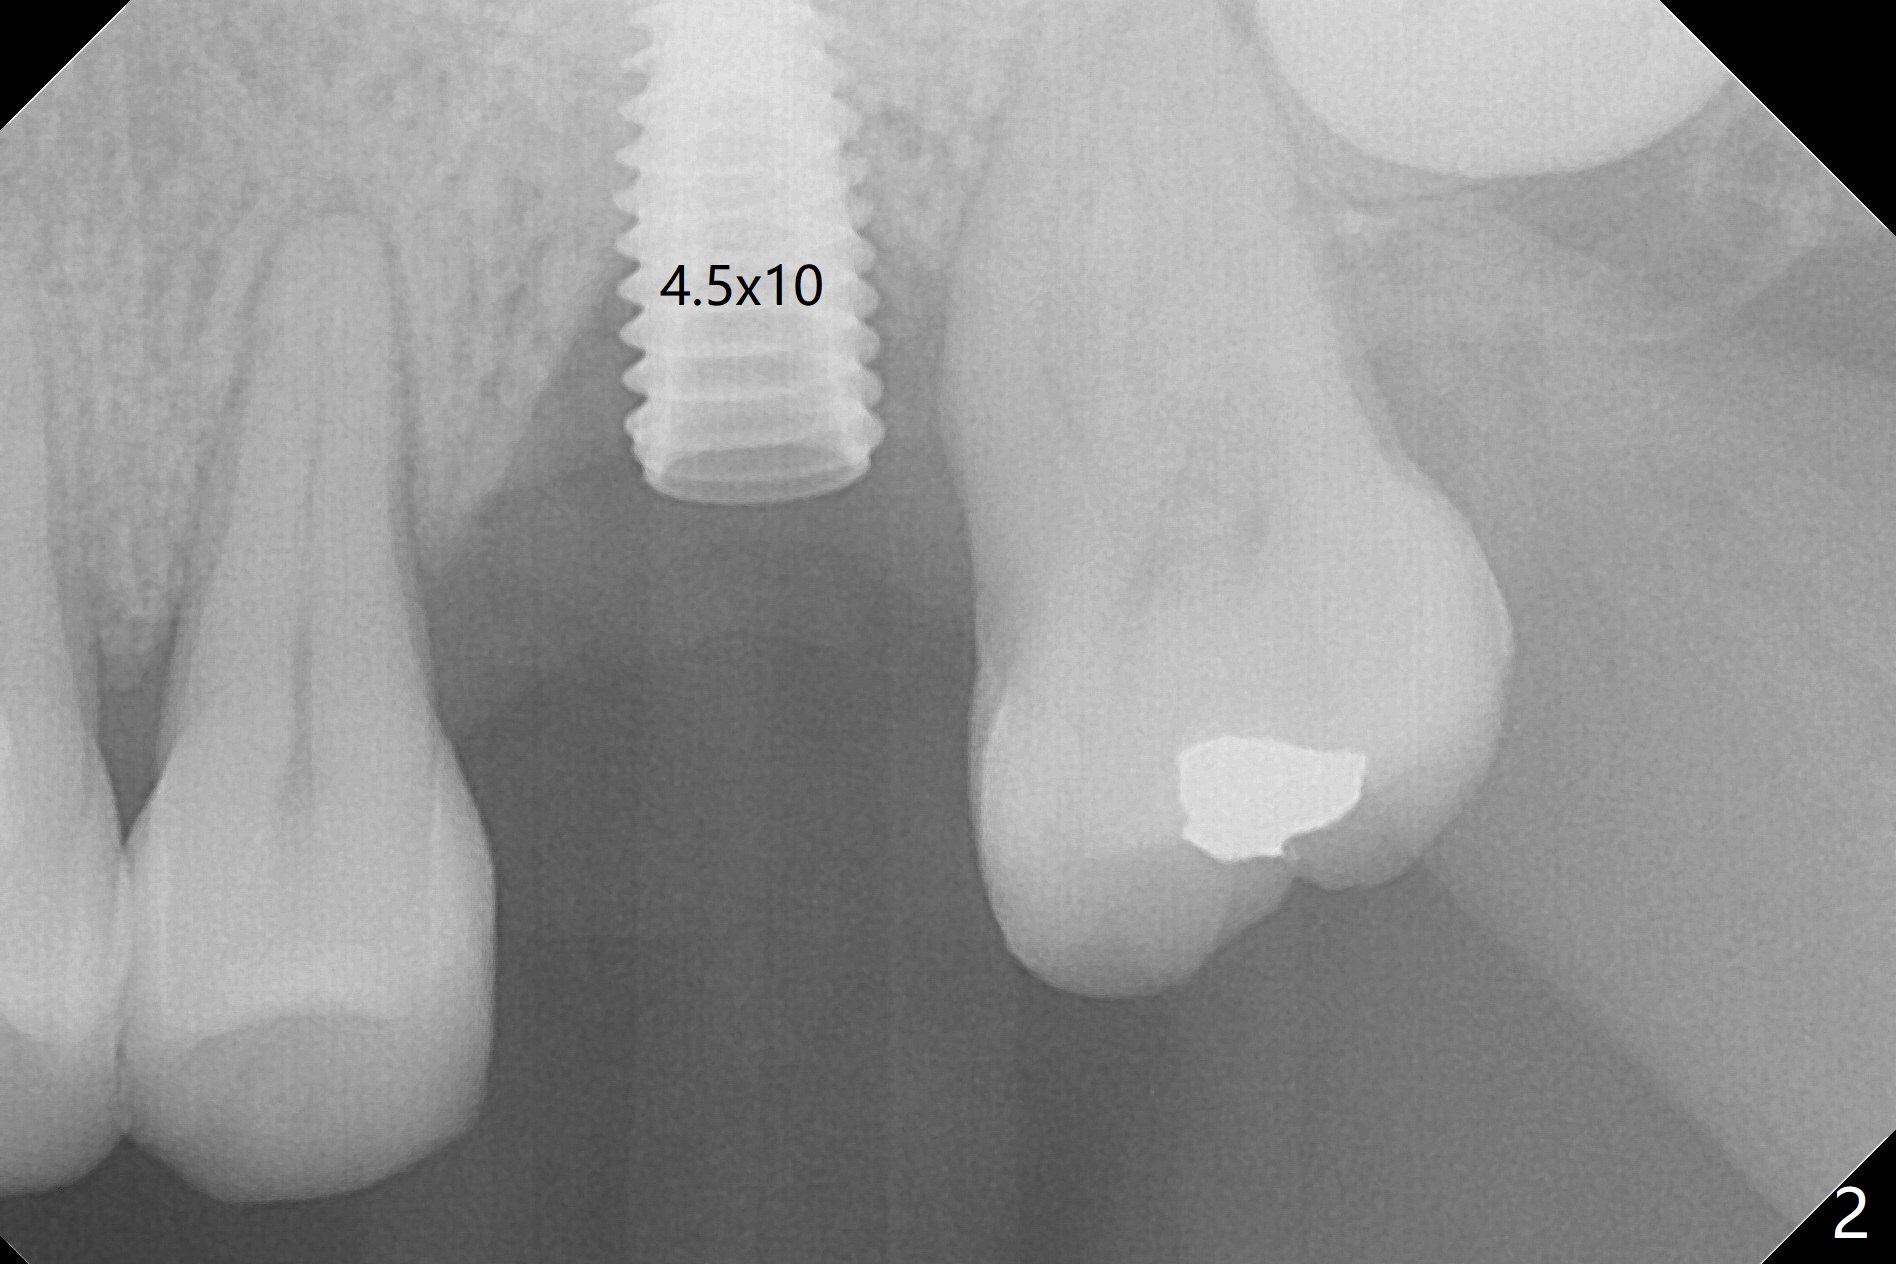

Redo: Shorter Implant Placed Deeper

with Better Surface Treatment

When an IBS implant with PAT surface (4.5x9 mm at #14; Fig.1 CT coronal section with ~ 7 mm bone height) is uncovered nearly 12 months postop, it is loose with a peri-implant space. Immediately post its removal and debridement, an IS dummy implant with SLA surface treatment (Fig.2: 4.5x10 mm) is placed. When a definitive implant is placed (Fig.3,4: 5x7.3 mm), it is subcrestal buccally and nearly equicrestal palatal. The remaining periimplant space is to be filled with demineralized cortical allograft. PAT: photo activated treatment (particles of calcium phosphate and a heating treatment). There is no apparent bone loss 3 months postop (Fig.5,6). The implant is uncovered with placement of a 5.7x4(4) mm cementation abutment and a nonfunctional provisional.